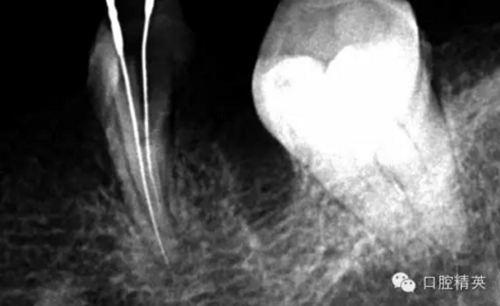

這個(gè)也是我目前接到最有難度的器械分離病例,從片子上看近中器械分離兩節(jié),曾在外院做過(guò)干尸,有七年。當(dāng)看到這個(gè)病例時(shí)我沒(méi)有多大的把握,因?yàn)槲沂巧硖幓鶎?,無(wú)顯微,無(wú)放大。我只有抱著試一試的態(tài)度,但是她是我們?cè)簝?nèi)員工,壓力很大。

現(xiàn)在開(kāi)始看第二張片子我疏通的遠(yuǎn)舌根,有點(diǎn)問(wèn)題哦!~

根尖孔偏移,或者是片子角度問(wèn)題,導(dǎo)致我們很難判斷,感覺(jué)像是測(cè)穿。但是我們有根測(cè)儀(前提它是好的),因?yàn)楦鶞y(cè)儀是我們目前對(duì)根管測(cè)量最具有說(shuō)服力,也是最為客觀事實(shí)的。根測(cè)儀沒(méi)有顯示一探入根尖下三分之一顯示“over”的情況(我用的是登士博根測(cè)儀)根管內(nèi)無(wú)滲出,可以測(cè)出根管的長(zhǎng)度。那就證明工作長(zhǎng)度的存在,和可信。在看看正題的近中根的器械,我想問(wèn)問(wèn)大家覺(jué)得是什么器械??